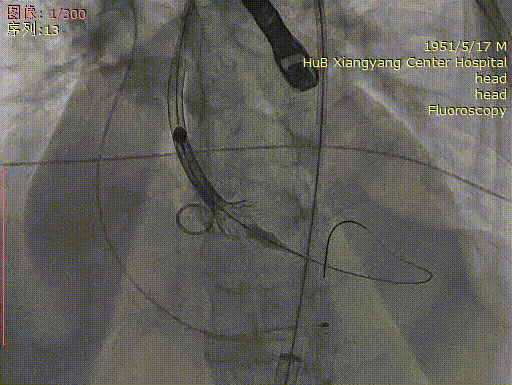

术中操作

主动脉根部造影

房间隔穿刺跨瓣

按压下完成球囊预扩

按压下完成瓣膜释放

释放后恢复心跳

最后造影

术中精彩瞬间